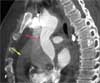

A second image with contrast is obtained just below the aortic arch, also in the axial plane (E). This image shows that the dissection extends to the level of the origin of the brachiocephalic artery (E, red arrow) and then stops. Again, the caliber of the descending aorta appears normal (E, yellow arrow). The brachiocephalic artery is also normal, as are the left subclavian and left common carotid arteries.